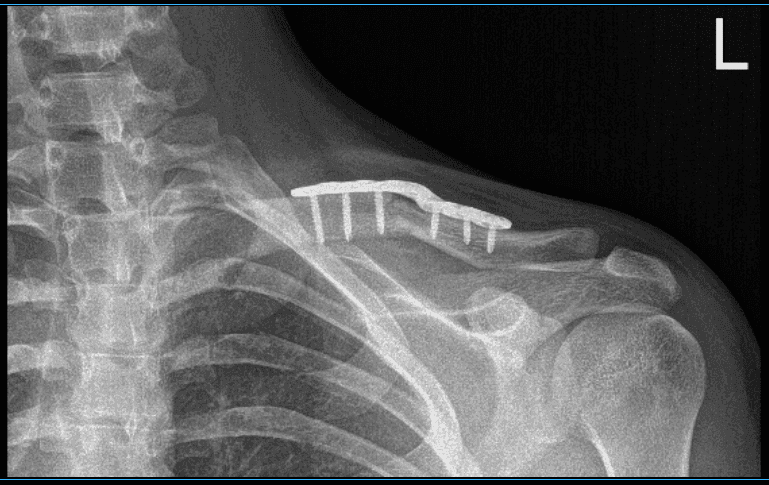

XR was presented in the office and found midshaft clavicular fracture with 1 cm overriding and moderate displacement. Midshaft Clavicle fractures are frequent traumatic injuries produced by a direct impact to the shoulder girdle, and they are most common in young, active adults.

Left Clavicle in AP position

Left Clavicle in axial position

With sharp and blunt dissection, the bone and the fracture site were reached and exposed. The fracture site was opened up and washed and cleaned with curette. The fracture was reduced and a superior plate was put. The plate was fixed proximally and medially with two screws process for lagging for compression.

Finally, the plate was put and compression was done using a compression screw. Two nonlocking g and one locking screw were used on either side. The final images were taken and found to be satisfactory. Final images were saved.

The patient was extubated and moved to the postoperative recovery unit in a stable condition. After two weeks, the patient checked in, with presented XR, and no periprosthetic lucency. The sternoclavicular joint demonstrates normal alignment.

4 weeks X-ray results of left clavicle after surgery

12 weeks X-ray results of left clavicle after surgery

14 weeks X-ray results of left clavicle after surgery